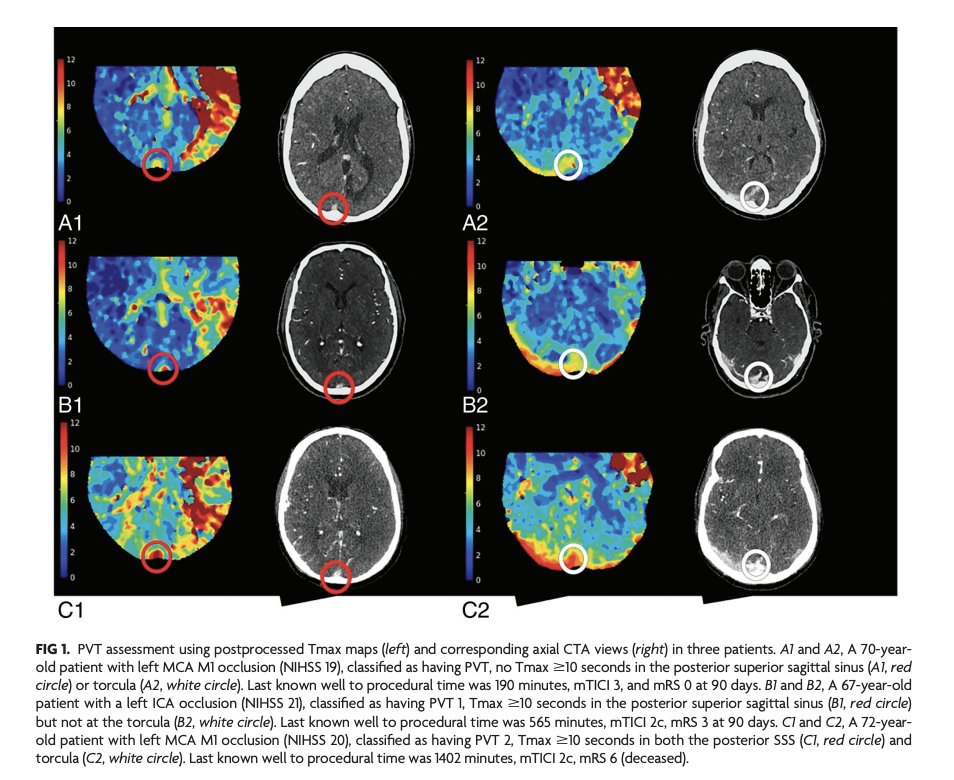

Honored to give Grand Rounds at @MGHNeuroRad @mghradchiefs on Imaging of Collateral Circulation in Stroke! Thank you to Javier, Ray, and Mike in particular for the opportunity and hospitality! @TheASNR @theASFNR @Hopkins_Rad @hopkinsneurorad #stroke #perfusion #venousoutflow